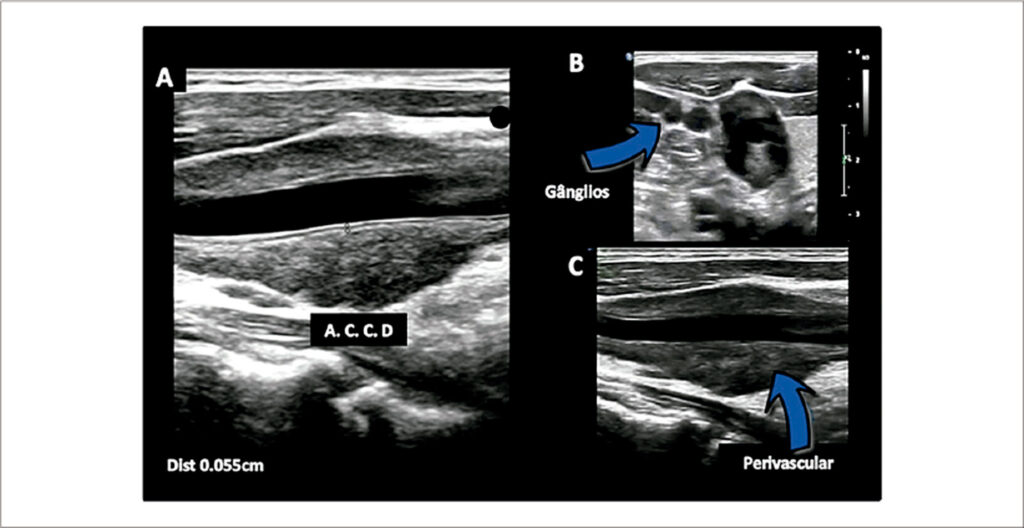

Achado Raro de Sarcoidose Pulmonar com Acometimento do Sistema Carotídeo Extracraniano

Na sarcoidose, ocorre um processo inflamatório não infeccioso que evolui para a formação de granulomas, acometendo predominantemente os pulmões e linfonodos intratorácicos em cerca de 90 a 95% dos casos. Cerca de 30% dos pacientes com sarcoidose apresentam envolvimento extrapulmonar, podendo ser a manifestação primária da doença ou, até mesmo, o único órgão acometido de forma isolada.–

Palavras-chave: Artérias Carótidas; Sarcoidose; Ultrassonografia